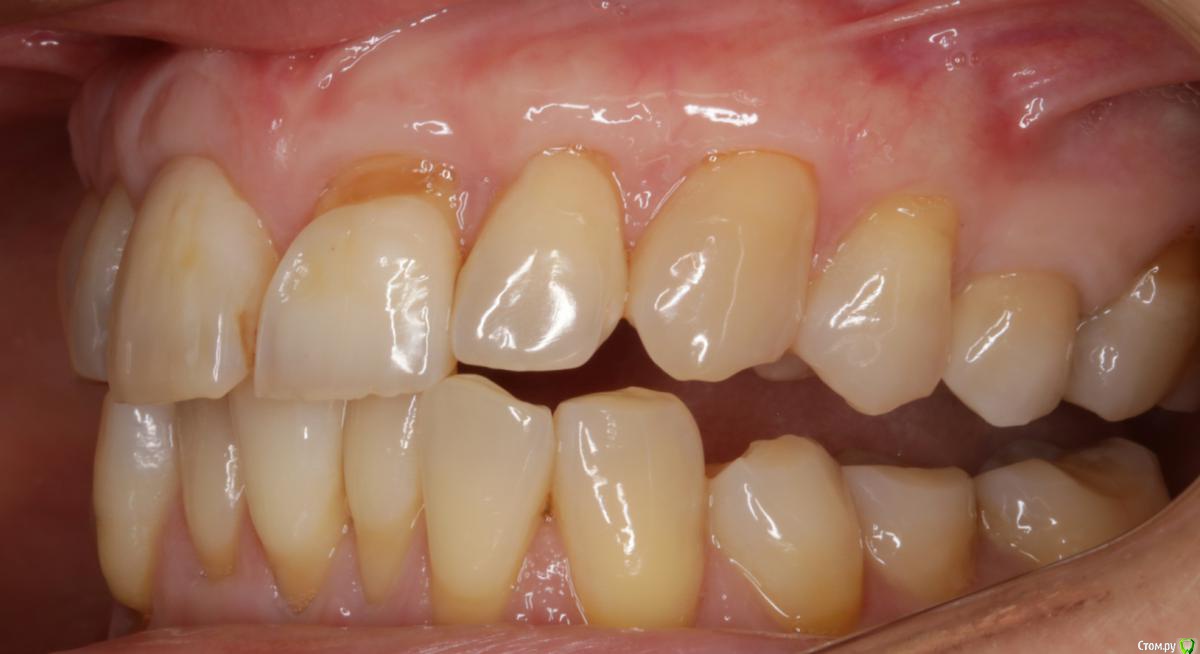

Dmitry DK Опубликовано 31 августа, 2019 Поделиться Опубликовано 31 августа, 2019 Доброго дня! Первичное обращение пациентки было связано с отсутствием 25 зуба, эстетические нарушения слизистой, клиновидные деф-ты в области других зубов - не смущали.В итоге решили, раз проводим операцию ( импл + ССТ ), закроем попутно и рец на верхней челюсти.Реставрацию на 21 зуб все не ставит... Приятных тебе выходных! ) Пациентка проходила лечение 2,5 года назад, пришла на проф осмотр 7 Ссылка на комментарий

Dmitry DK Опубликовано 2 сентября, 2019 Автор Поделиться Опубликовано 2 сентября, 2019 ничего себе попутно, в итоге на имплант 15 минут, а на рецессии 2 часа?))У меня те же мысли были), но согласитесь, что если бы мы этого не сделали - разница в зенитах былабы слишком велика Ссылка на комментарий

Bier Опубликовано 3 сентября, 2019 Поделиться Опубликовано 3 сентября, 2019 в итоге наврали с зенитом на имплантате. Ссылка на комментарий

Bier Опубликовано 3 сентября, 2019 Поделиться Опубликовано 3 сентября, 2019 что вы имеете ввиду?короткий зуб, что же еще. Ссылка на комментарий

Dmitry DK Опубликовано 4 сентября, 2019 Автор Поделиться Опубликовано 4 сентября, 2019 короткий зуб, что же еще.У имплантата край дёсны действительно корональнее.Платплатформа в двух миллиметрах от цементо-эмалевой границы, была возможность иссечь излишек либо его ещё отдавить, также как хотелось заполировать в 1-м сегменте, поставит реставрацию на 21-м и т.д.Пациентка отказалась от дальнейших этапов... Ссылка на комментарий